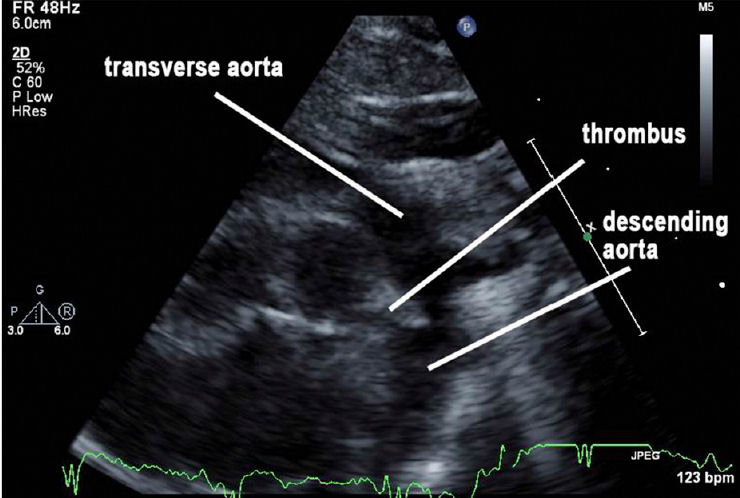

Un hallazgo incidental de trombo del ductus arterioso que se extiende a arteria pulmonar principal y arteria pulmonar izquierda se descubrió en la ecocardiografía (Figuras 1 y 2).

Figura 2.- Las imágenes ecocardiográficas capturadas a lo largo de la vista supraesternal de la muesca demuestran el arco aórtico. Aquí se ve el trombo del ducto arterioso permeable que sobresale en la aorta descendente.